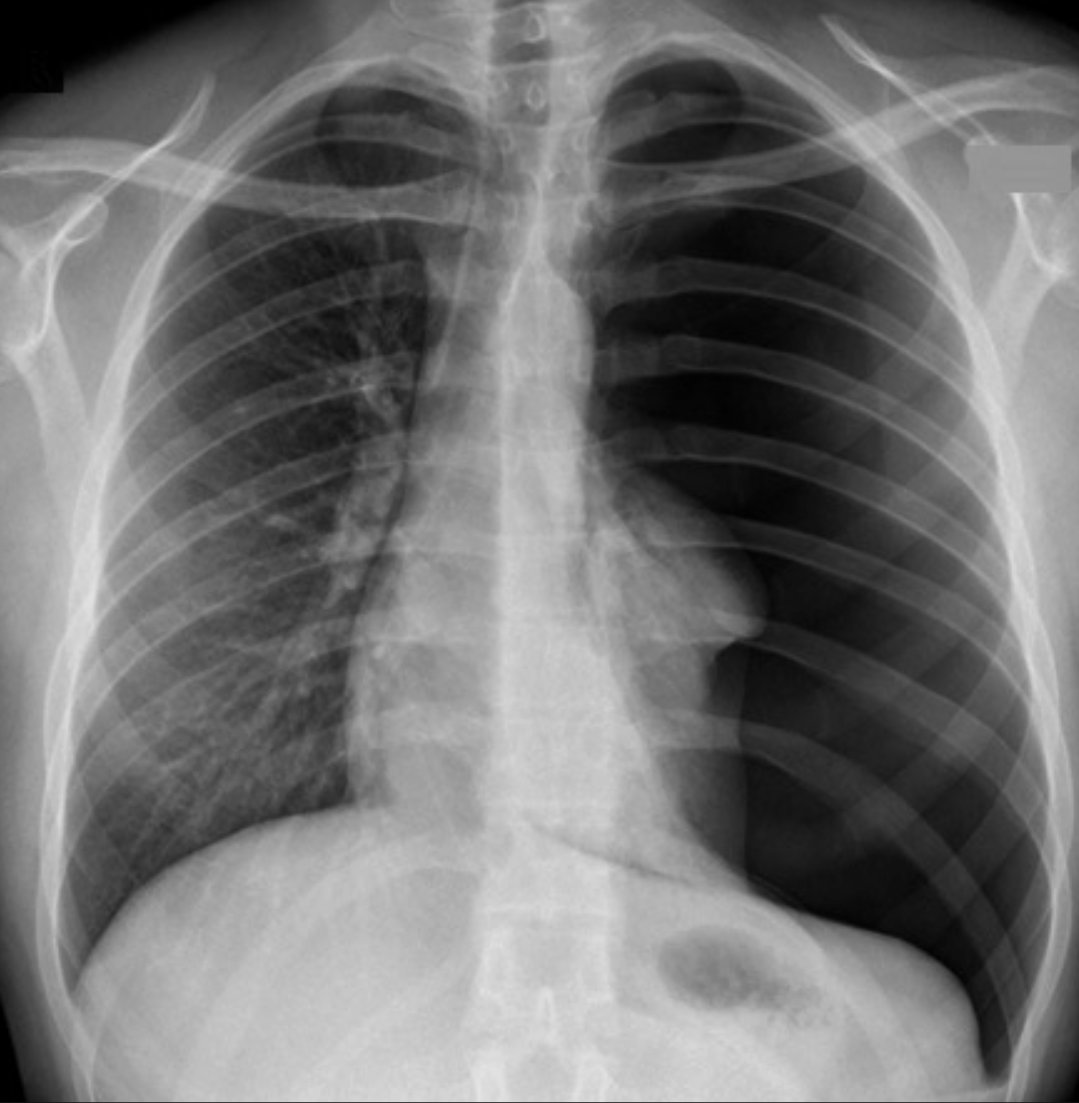

If I’m gonna get really specific with this one, this is a tension pneumothorax on the left, which needs IMMEDIATE needling for relief and then conversion to a closed tube thoracostomy. Patients with this are in distress, have difficulty breathing, are desaturating, tachycardic…

Just admitted a healthy early20's guy with no past medical history who presented with sudden chest pain after hitting his vape. CXR looks like the example pic: What's the diagnosis?